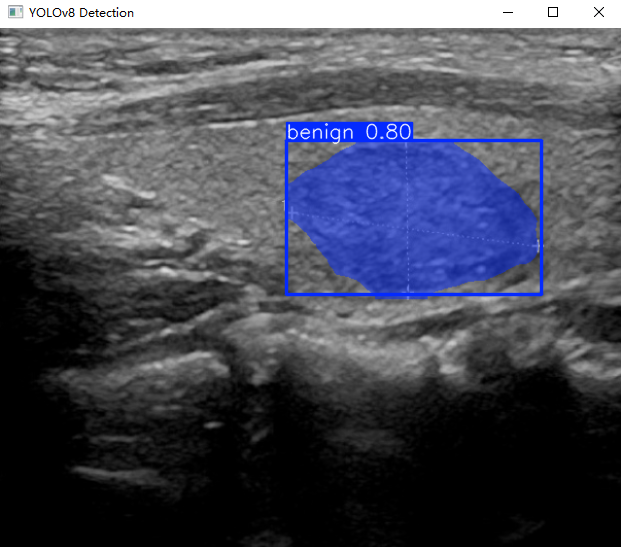

cv2.imshow("YOLOv8 Detection", res)

执行上述代码后,会将执行的结果直接标注在图片上,结果如下: